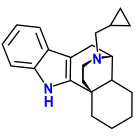

Oripavine derivatives

Thienorphine

- 7-PET

- Acetorphine

- Alletorphine (N-allyl-noretorphine)

- BU-48

- Buprenorphine

- Buprenorphine-3-glucuronide

- Cyprenorphine

- Dihydroetorphine

- Etorphine

- Homprenorphine

- 18,19-Dehydrobuprenorphine (HS-599)

- N-cyclopropylmethylnoretorphine

- Nepenthone

- Norbuprenorphine

- Norbuprenorphine-3-glucuronide

- Thevinone

- Thienorphine

Structures

| Oripavine derivatives | ||||

|---|---|---|---|---|

7-PET 7-PET |

Acetorphine Acetorphine |

Alletorphine Alletorphine |

BU-48 BU-48 |

Buprenorphine Buprenorphine |

Cyprenorphine Cyprenorphine |

Dihydroetorphine Dihydroetorphine |

Etorphine Etorphine |

Homprenorphine Homprenorphine |

18,19-Dehydrobuprenorphine 18,19-Dehydrobuprenorphine |

N-cyclopropylmethylnoretorphine N-cyclopropylmethylnoretorphine |

Nepenthone Nepenthone |

Norbuprenorphine Norbuprenorphine |

Thevinone Thevinone |

Thienorphine Thienorphine |